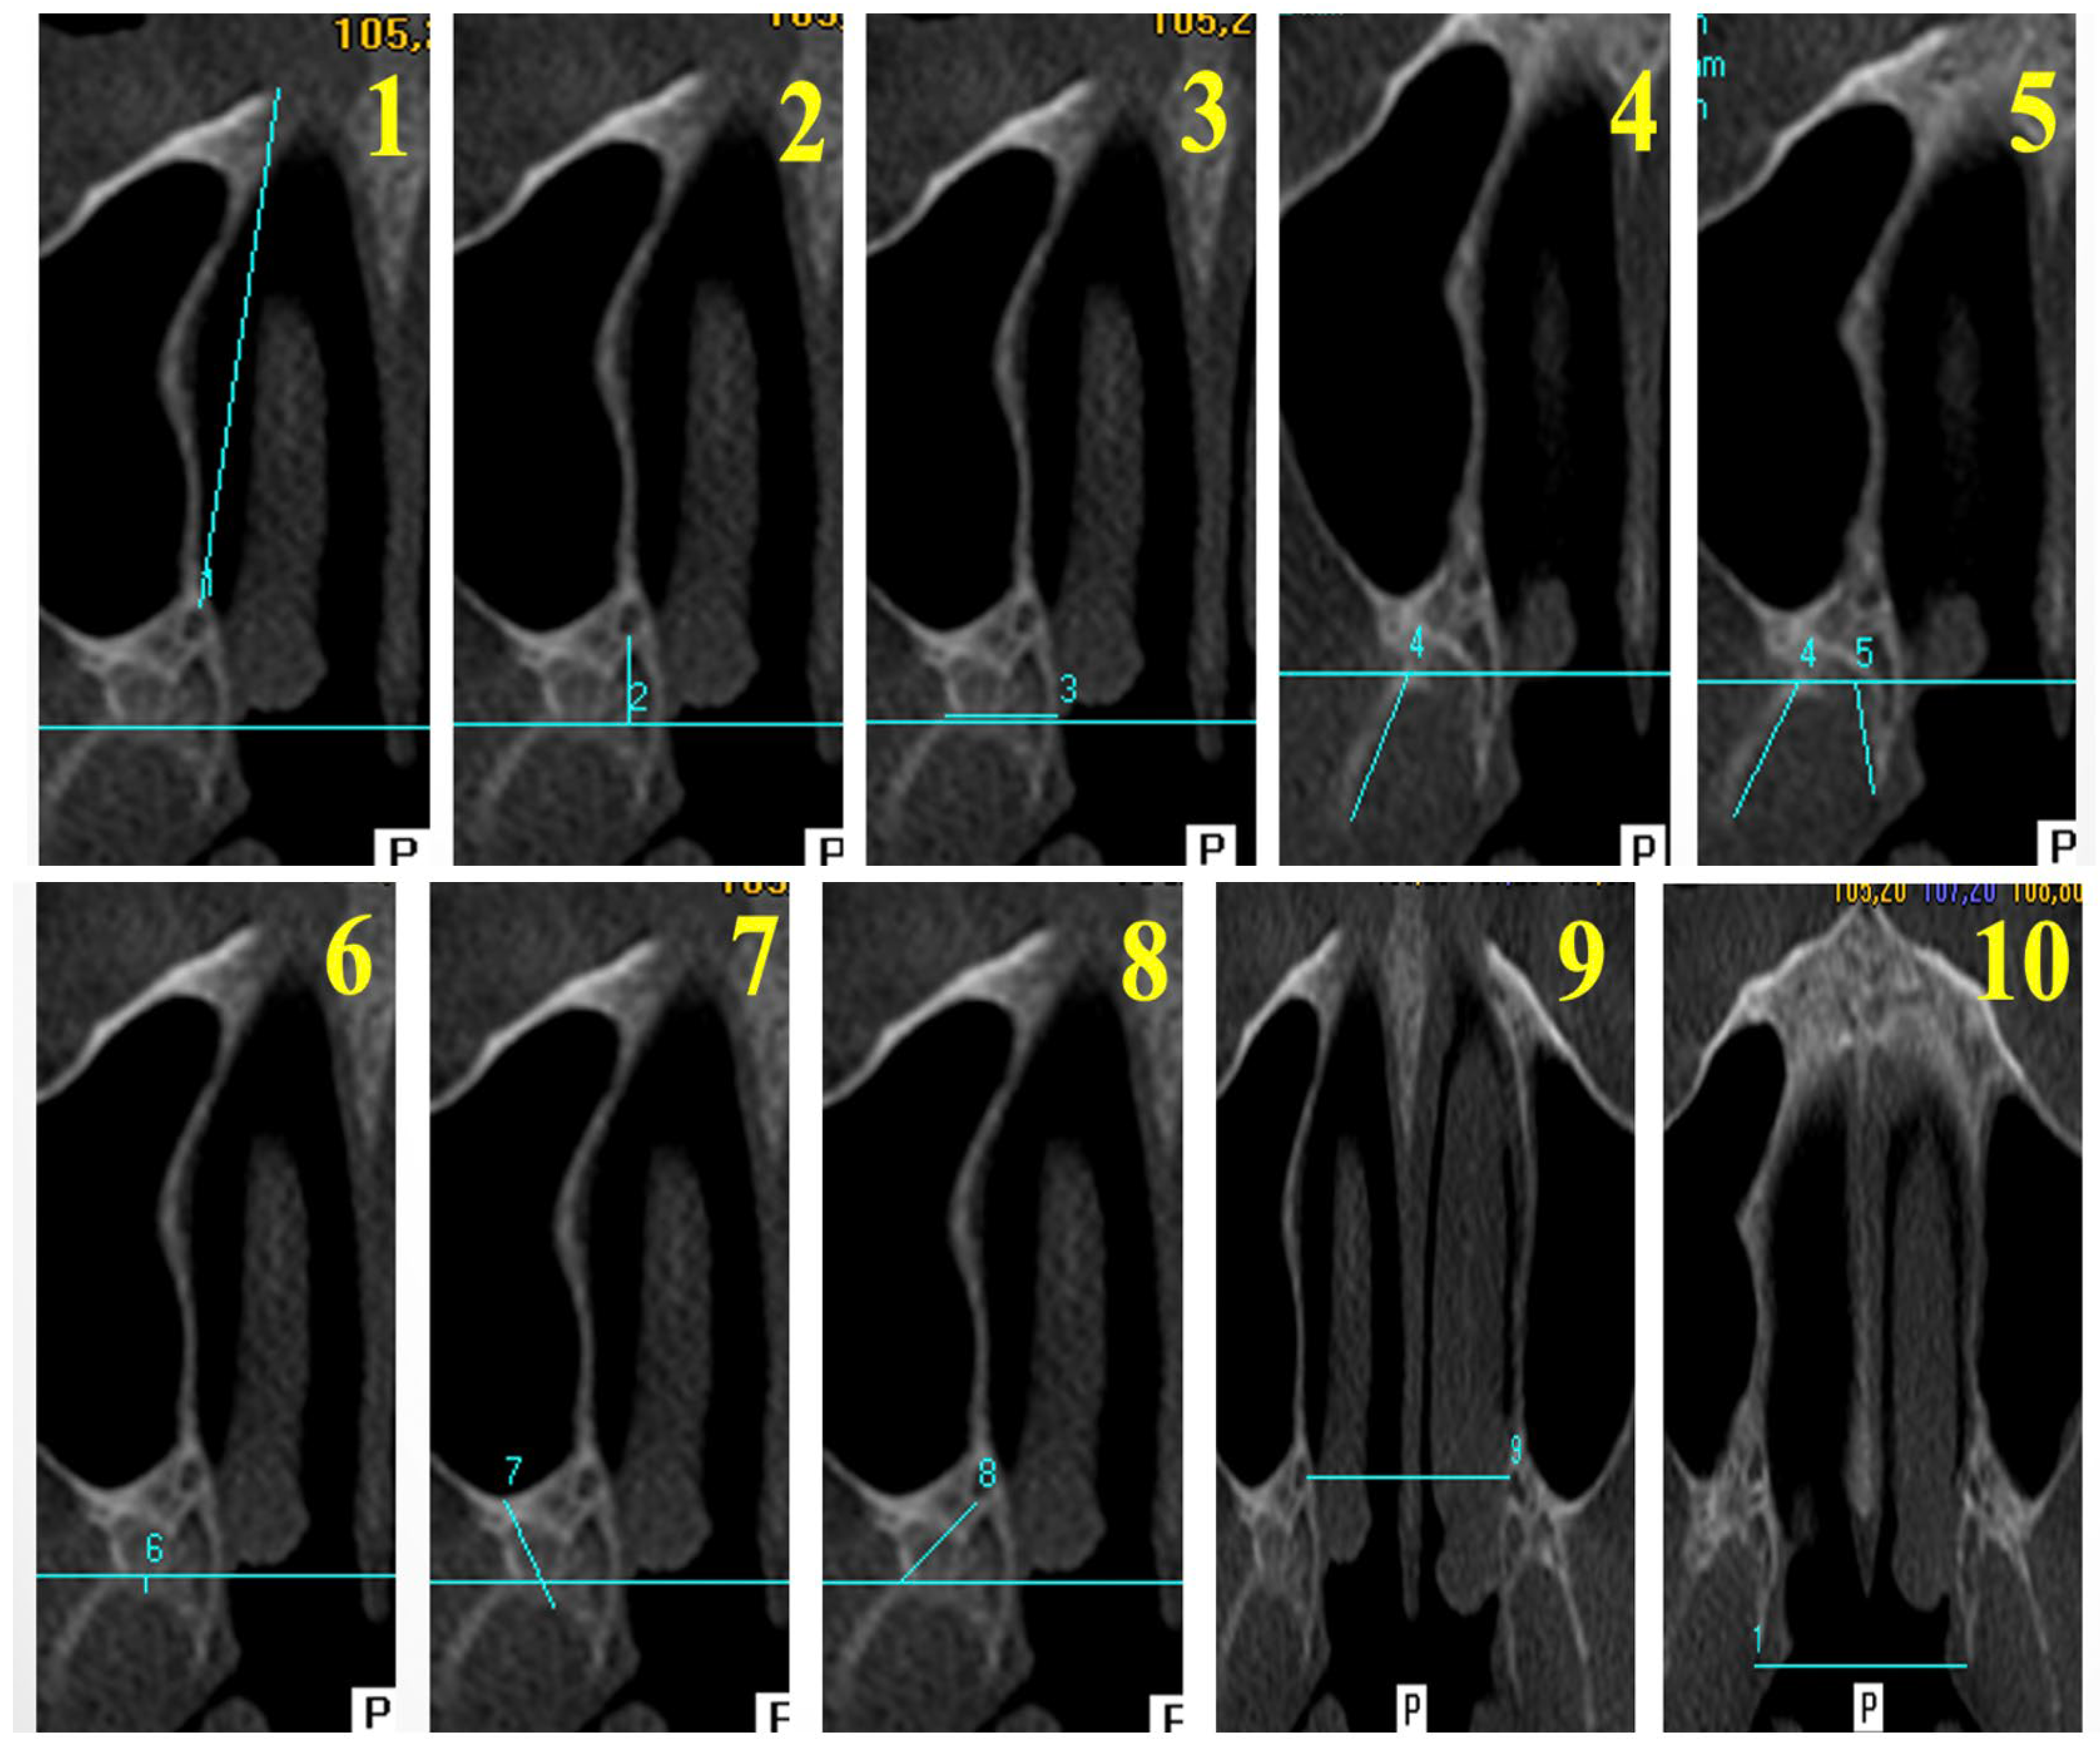

2.3. Measured Morphometric Parameters

| ABBREVİATİON | PARAMETER NAME | DEFİNİTİON |

|---|---|---|

| Anterior Length (AL) | Anterior Length Measurements | Distance from the descending palatine artery to the piriform rim |

| Posterior Length (PL) | Posterior Length Measurements | Distance from the posterior point of the greater palatine canal to the deepest concavity of the pterygomaxillary fissure |

| Pterygoid Process Width (PPW) | Measurements of Pterygoid Process Width | Minimum width of the pterygoid process along the pterygomaxillary fissure line |

| Lateral Lamina Length (LLL) | Measurements of Lateral Pterygoid Lamina Length | Distance from the deepest concavity of the pterygomaxillary fissure to the posterior-most point of the lateral lamina |

| Medial Lamina Length (MLL) | Measurements of Medial Pterygoid Lamina Length | Distance from the most medial point of the fissure to the posterior end of the medial lamina |

| Pterygoid Process Thickness (PPT) | Measurements of Pterygoid Process Thickness | Distance from the deepest point of the pterygoid fossa to the pterygomaxillary fissure |

| Pterygomaxillary Region Thickness (PMT) | Measurements of Pterygomaxillary Region Thickness | The minimum distance between the posterior wall of the maxillary sinüs and the deepest point of the pterygoid fossa |

| Distance Fissure to Greater Palatine Canal (DF–GPC) | Measurements of the Distance Between the Pterygomaxillary Fissure and the Greater Palatine Canal | Distance from the most concave point of the lateral portion of the pterygomaxillary fissure to the greater palatine canal |

| Distance Between Greater Palatine Canals (DGPC) | Measurements of the Distance Between the Bilateral Greater Palatine Canals | Distance between the most medial points of the right and left greater palatine canals |

| Distance Between Medial Lamina Endpoints (DML) | Measurements of the Distance Between the Bilateral Medial Lamina Endpoints | Distance between the medial lamina endpoints of the right and left pterygoid processes |